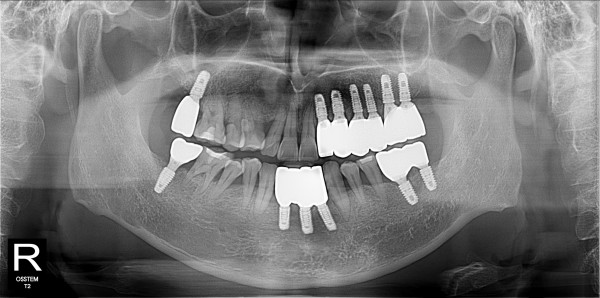

구치부 임플란트 최고관리자 0건 23-11-07 18:30 본문 구치부 임플란트 + 전치부 크라운 목록 이전글구치부 임플란트 23.11.07 다음글구치부 임플란트 23.11.07 댓글목록 0 댓글목록 등록된 댓글이 없습니다.